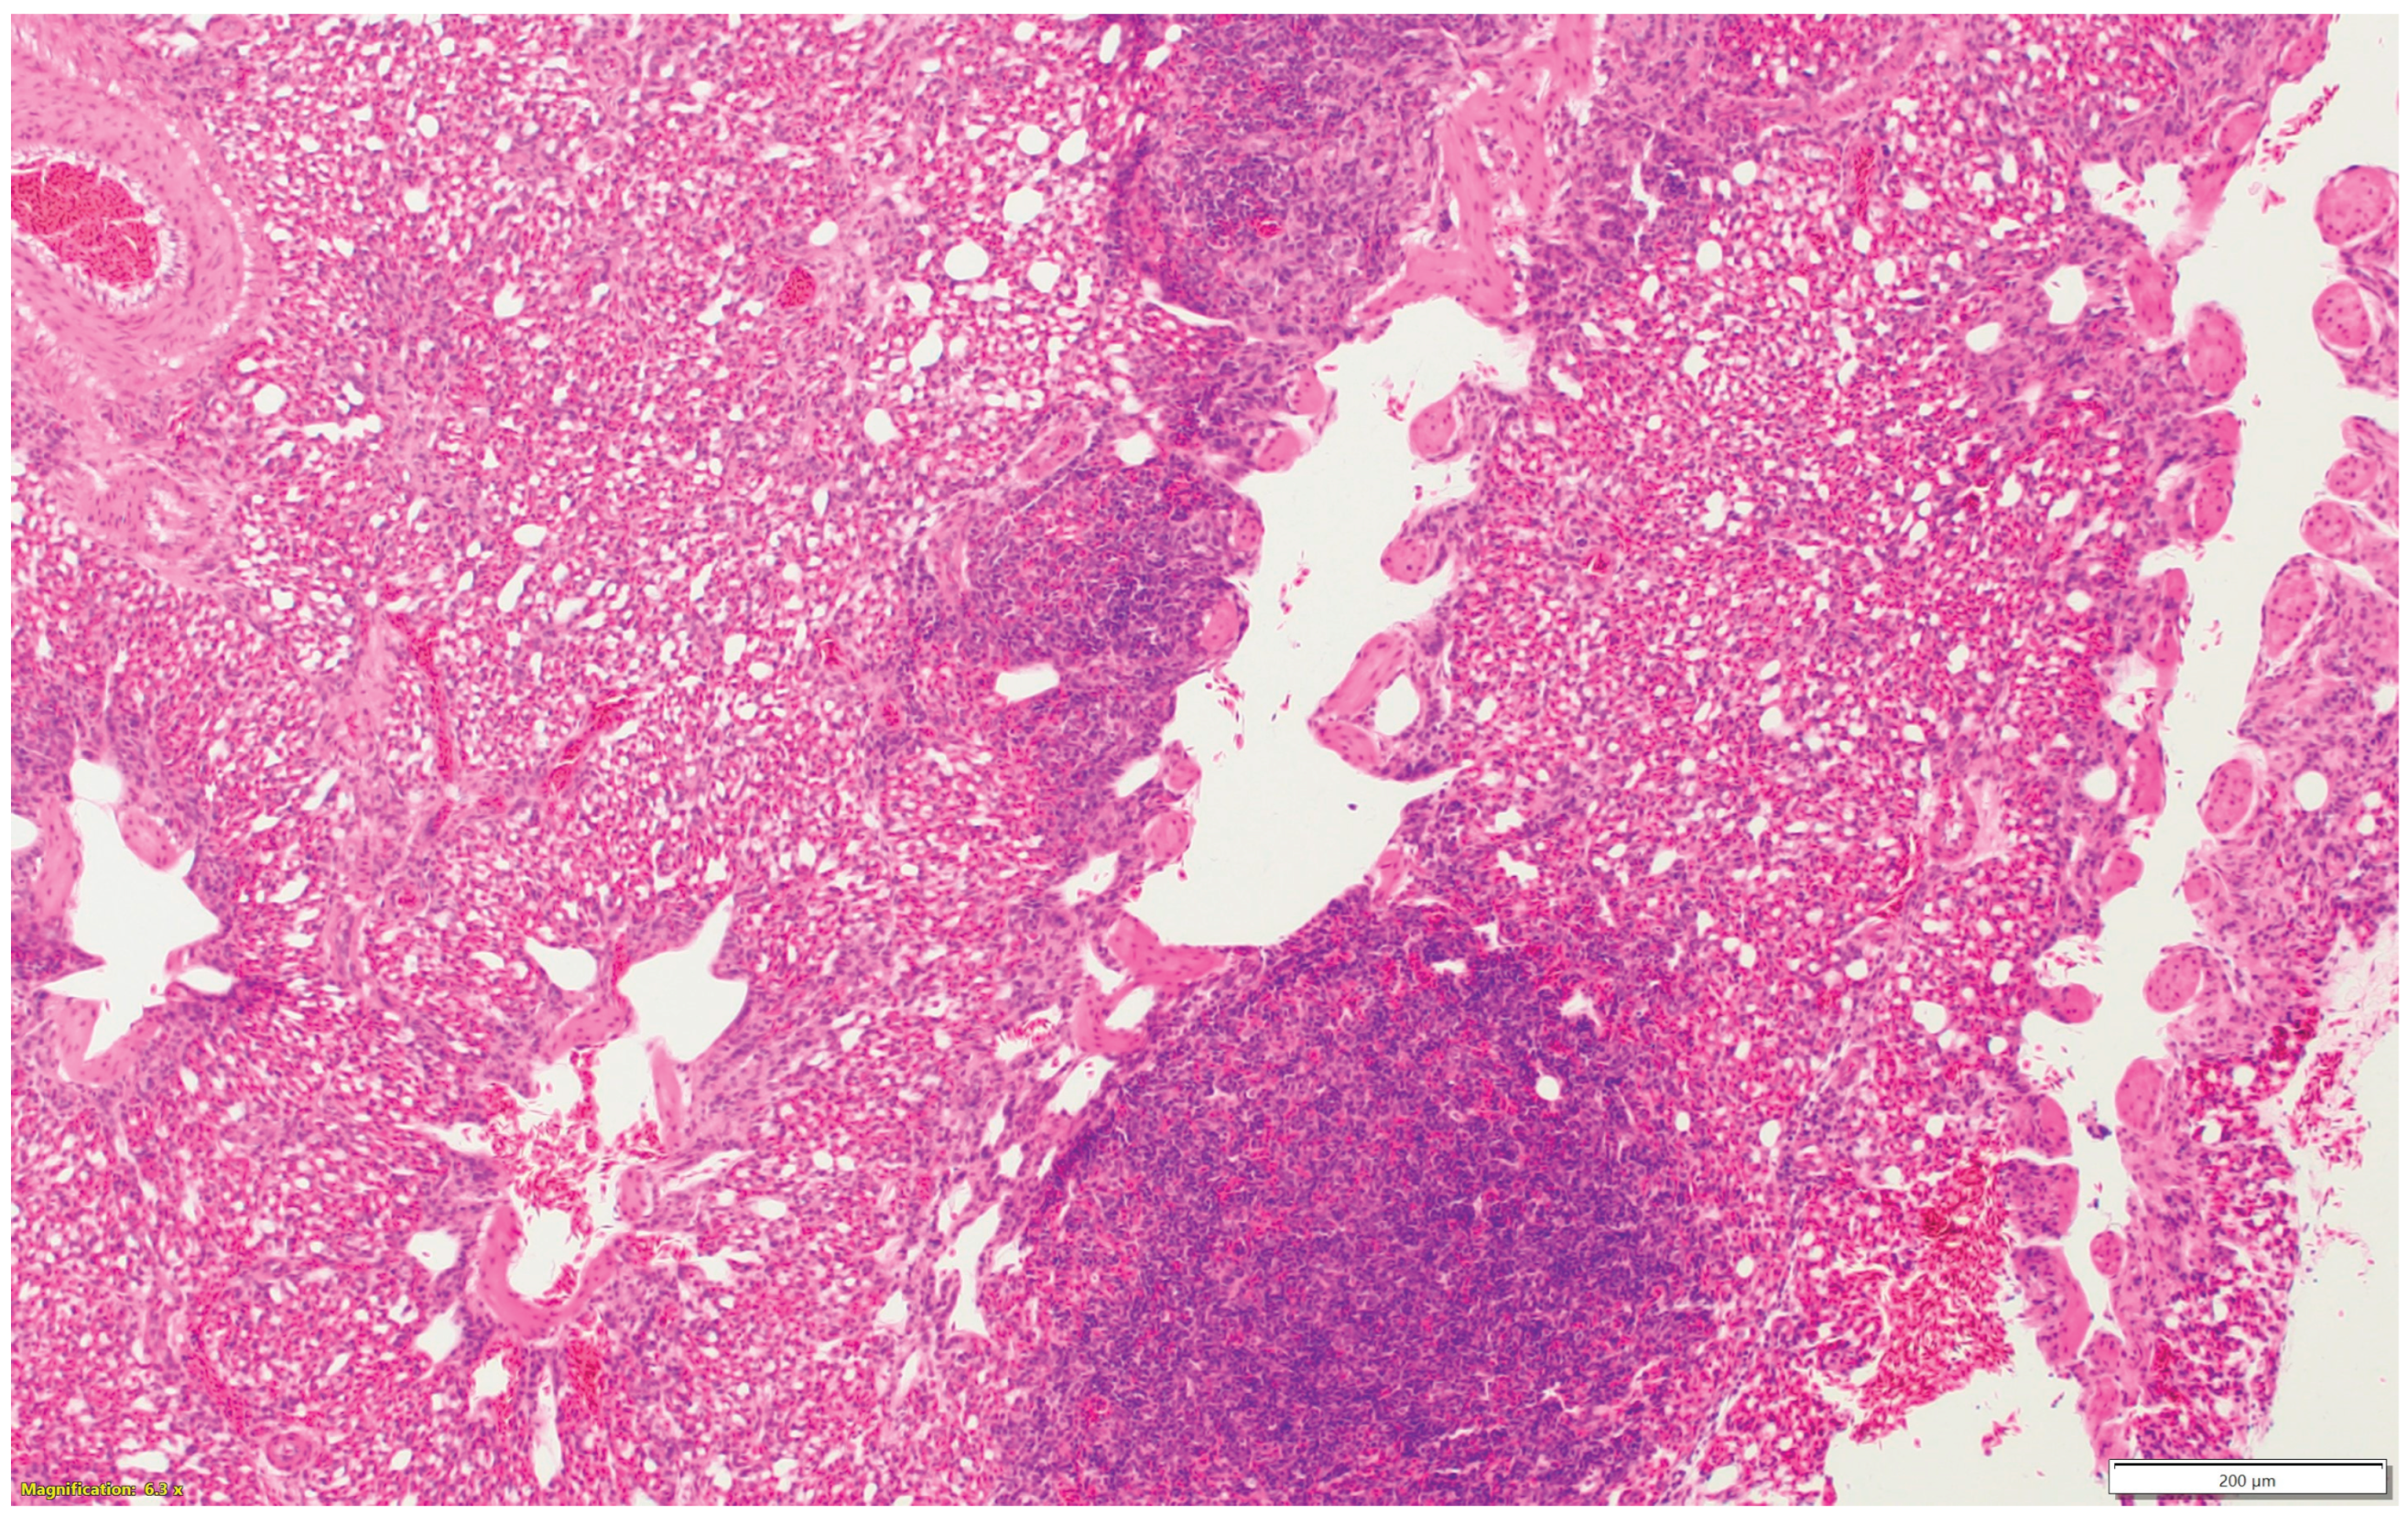

3.3. Turkeys inoculated with aMPV at 7 days of age showed higher lesion scores at 10 DPI compared with the non-infected control group. Sinus and eyelids were the main organs scoring points compared with other organs (Figure 4a).

3.4. Turkeys inoculated with low pathogenic avian influenza (LPAI-H4N6) at 7 days of age had also increased histologic lesion scores at 7 DPI compared with the non-infected control group. Sinus, lungs, eyelids, and trachea were orderly contributing to a higher total HRI (Figure 4b).